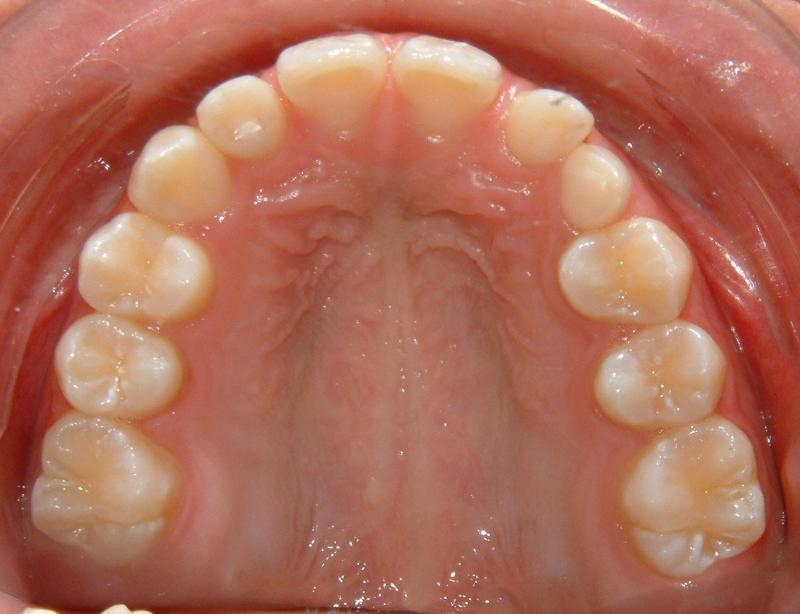

The progress of tooth eruption is complete (Fig. 24). Note that the crown of the tooth (lower left canine) is surrounded by healthy gingiva.

Fig. 24 Complete eruption, healthy gingiva, 9 months after surgical exposure (progress)

© Copyright 2007-2014, Vu Orthodontics. All rights reserved.